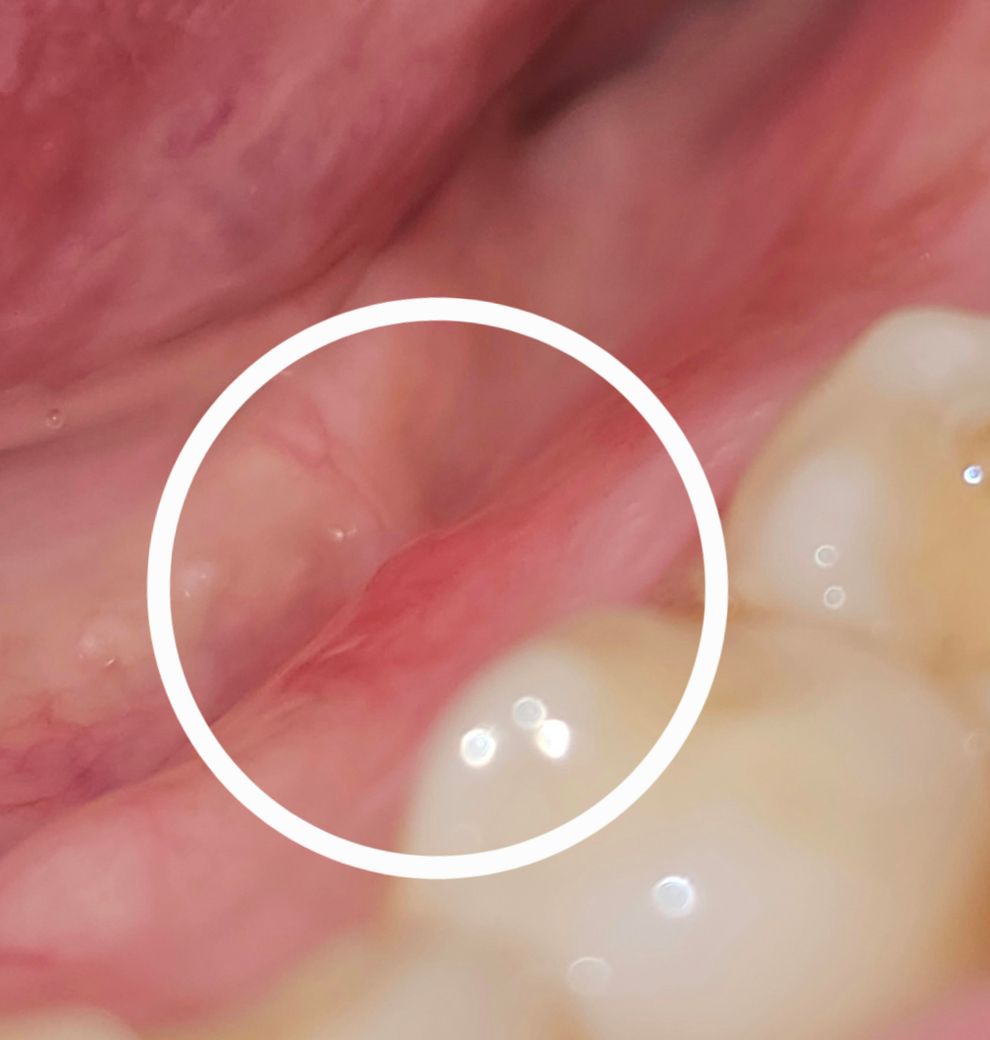

임플란트 옆 잇몸에 물집? 같은게 났어요..

임플란트 식립한곳 옆 치아 잇몸에 동글한게 느껴져서 보니

사진에는 잘 안나왔는데

화살표시 끝부분에 하얗게 살짝 2개 정도 튀어나와있고,

혀로 만지면 말랑말랑하고 동글동글한 뭔가가

2개 있어요..

아프지는 않아요.

혹시 물집인가요? 염증일까요?